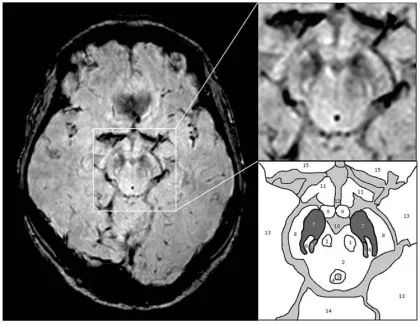

正常情况下燕尾征-SWI 的显示:从上至下连续 1-5 层,黑质(SN)出现 5 层,红核(RN)出现 4 层,黑质背外侧部高信号一般位于位于黑质的后 1/3,在红核最后一层或消失的层面出现。

PD、MSA 和 PSP 出现燕尾征-SWI 高信号的消失

燕尾征-SWI 高信号的消失对于鉴别神经退行性变和非退行性病变可能具有意义,但是对于鉴别帕金森病与帕金森综合征还是缺乏准确性的。